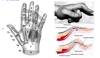

What are the components of the TFCC

-

dorsal and volar radioulnar ligaments

- deep ligaments known as ligamentum subcruatum

- central articular disc

- meniscus homolog

- ulno-lunate; ulno-triquetral (UCL)

- ECU subsheath

- origin of ulnolunate and ulnotriquetral ligaments

What are the primary stabilizers of the DRUJ

-

Primary

-

volar radioulnar ligaments

- volar translation

- supination

-

dorsal radioulnar ligaments

- dorsal translation

- pronation

- trigangular fibrocartilage

volar radioulnar ligaments

Secondary

- ulnar head

- sigmoid notch

- interosseous membrane

- pronator quadratus